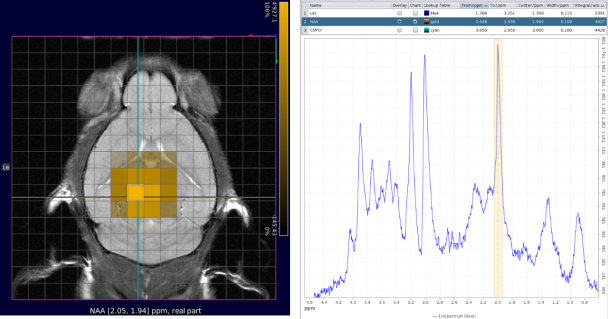

- Efficient visualization and processing of single-voxel spectroscopy and chemical shift imaging spectroscopic data (e.g., CSI) with Spectroscopy Card

- Metabolic map creation and anatomical reference image overlaying

- Spectral editing of J-coupled resonances such as lactate, γ-aminobutyric acid (GABA), glutamate, and glx (glutamate/glutamine) with MEGA-PRESS

CSI with NAA frequency mapped. Image Credit: Bruker BioSpin Group